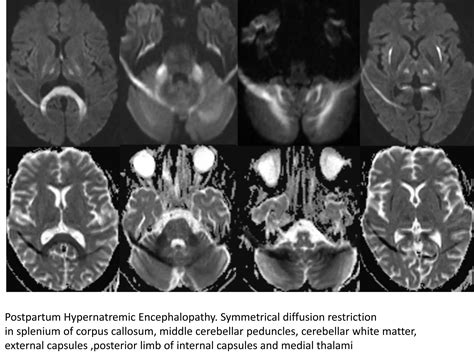

• Electrolyte Imbalances: Severe hyponatremia (low sodium), hypercalcemia, or disturbances in potassium levels significantly alter neuronal membrane potential, disrupting signal transmission.

• toxic metabolic encephalopathy radiology